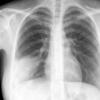

Case 1 Round pneumonia

Date: 04/16/2005

Views: 8080